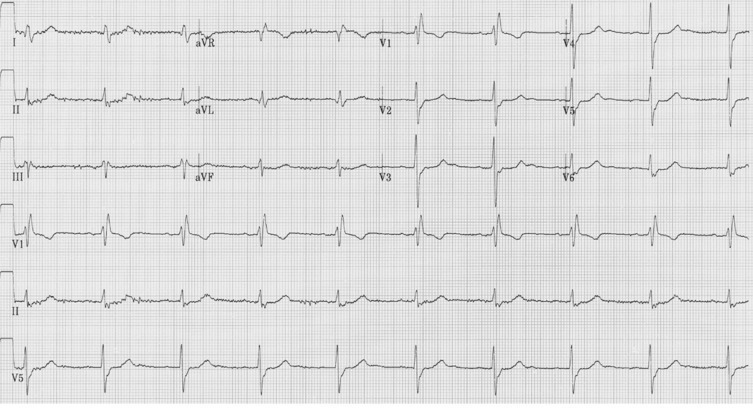

Question 2 - L’ECG montre (une ou plusieurs réponses exactes) :

L’ECG montre une tachycardie régulière à QRS fin, donc retenir surtout 4 causes possibles :

– tachycardie sinusale (appropriée ou inappropriée) : onde P sans ondes P bloquées ;

– flutter auriculaire (onde de macro-réentrée isthme cavo-triccuspidien dépendante) : ondes en dent de scie SANS à la ligne iso-éléctrique. Négatives en inférieur en cas de flutter typique antihoraire ;

– tachycardie atriale focale ;

– tachycardie jonctionnelle.